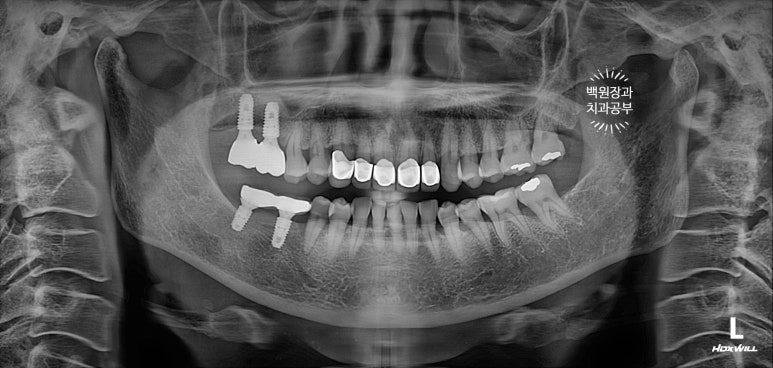

교합면에서 보았을 때 제작해드렸던 임플란트 크라운도 깔끔하게 잘 관리하고 계셨습니다.

3년이 지나니 상악동 뼈이식술을 했던 곳은 이제 거의 내 뼈와 하나가 된 것처럼 예쁘게 성숙된 모습을 보여주고 있고, 앞니 지르코니아 크라운은 꼼꼼히 관리해주신 덕분에 충치 하나 없이 신경치료 하지 않았음에도 아주 잘~ 쓰고 있는 모습을 확인할 수 있었습니다!